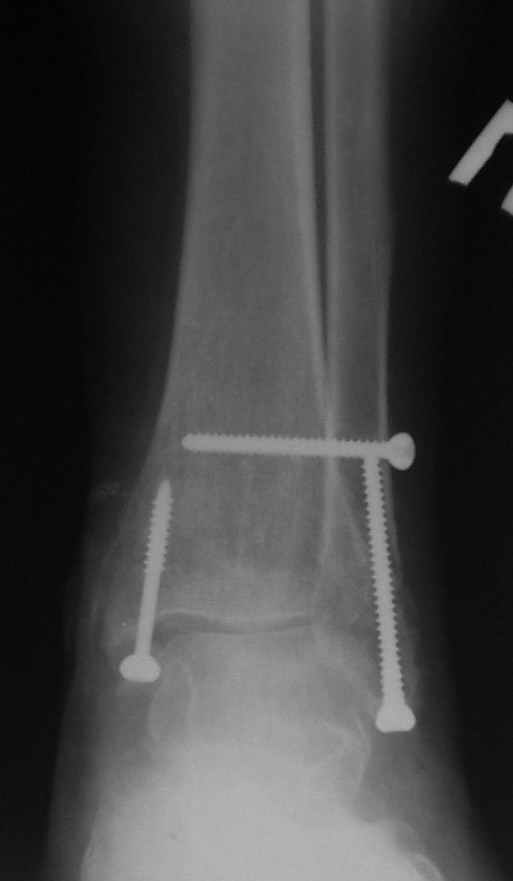

Ниже рентгенограммы

До операции 28 июля

Операция 29 июля

Через месяц

Боковой через месяц

15 ноября прямой

15 ноября боковой

15 ноября трехчетвертной

12 января прямой

12 января боковой

12 января трехчетвертной

Риторический вопрос - в каком руководстве рекомендован такой способ остеосинтеза наружной лодыжки?

Очевидно, такой результат операции был запрограммирован. При невосстановленной длине и практически нефиксированной малоберцовой кости (этот кортикальный винт - как карандаш в стакане), при неустраненном подвывихе, невправленной и тоже нефиксированной внутренней лодыжке нет стабильной вилки сустава. Если такую операцию сделать даже сразу, а не через 4 месяца, то результат ожидаем

тот же.

Если до сих ничего не сделано, с артродезом сустава в данный момент я бы повременил, на выставленных январских снимках хорошо сохранившийся сустав, а в "мортиз" (трехчетвертной) и на боковых снимках не менее 5 мм укорочение малоберцовой кости. Косые переломы лучше фиксировать пластинами, как то мы разбирали случай, где было отмечено, что это закон "таранная кость всегда следует за малоберцовой".